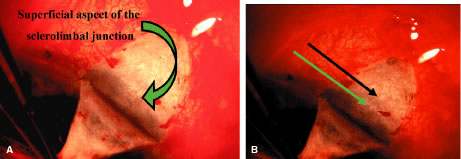

To obtain increasingly lower IOP, it is necessary to modify surgical technique (Table 15). By performing guarded filtration procedures so that the sutures can be released postoperatively, with the use of either laserable or releasable sutures, a lower final IOP can be obtained in some cases. This technique allows a bleb to develop that is similar to that seen in a full-thickness filtration procedure. Such blebs tend to be thin, polycystic, and located directly at the limbus, in contrast to those seen after classic trabeculectomy, which are thicker, lower, more diffuse, and more posterior. When antifibrosis agents (antimetabolites and corticosteroids) are added to procedures designed to develop full-thickness filtration, IOP tends to be sharply reduced.27–29 The blebs associated with the use of 5-fluorouracil (5-FU) and mitomycin are an exaggeration of the full-thickness type of bleb: Often, they are extensive, sometimes involving 360 degrees of the anterior surface of the globe, and the conjunctiva tends to be thin and completely ischemic.30–34

The thin filtration blebs associated with the use of mitomycin or 5-FU may rupture spontaneously. They tend to be so high that the adjacent cornea becomes dry, with the development of an uncomfortable delle. Ptosis tends to develop, and patients often are photophobia One of the most serious concerns is the high incidence of endophthalmitis in patients with thin blebs. When full-thickness blebs were the routine type of glaucoma procedure, endophthalmitis would develop in approximately 1% of patients. When 5-FU was used to develop filtration blebs inferiorly, an 8% rate of endophthalmitis was reported.35–42 Hypotony, even in the absence of a thin bleb, introduces serious problems. The soft eye does not maintain a constant optical state, and it has a constantly changing amount of astigmatism that makes it impossible to correct. Each time the patient blinks, the amount of astigmatism changes. Macular and disc edema cause reduced central acuity and deterioration of the visual field, and the globe may have a constant, visceral ache. Patients with such eyes are not comfortable.